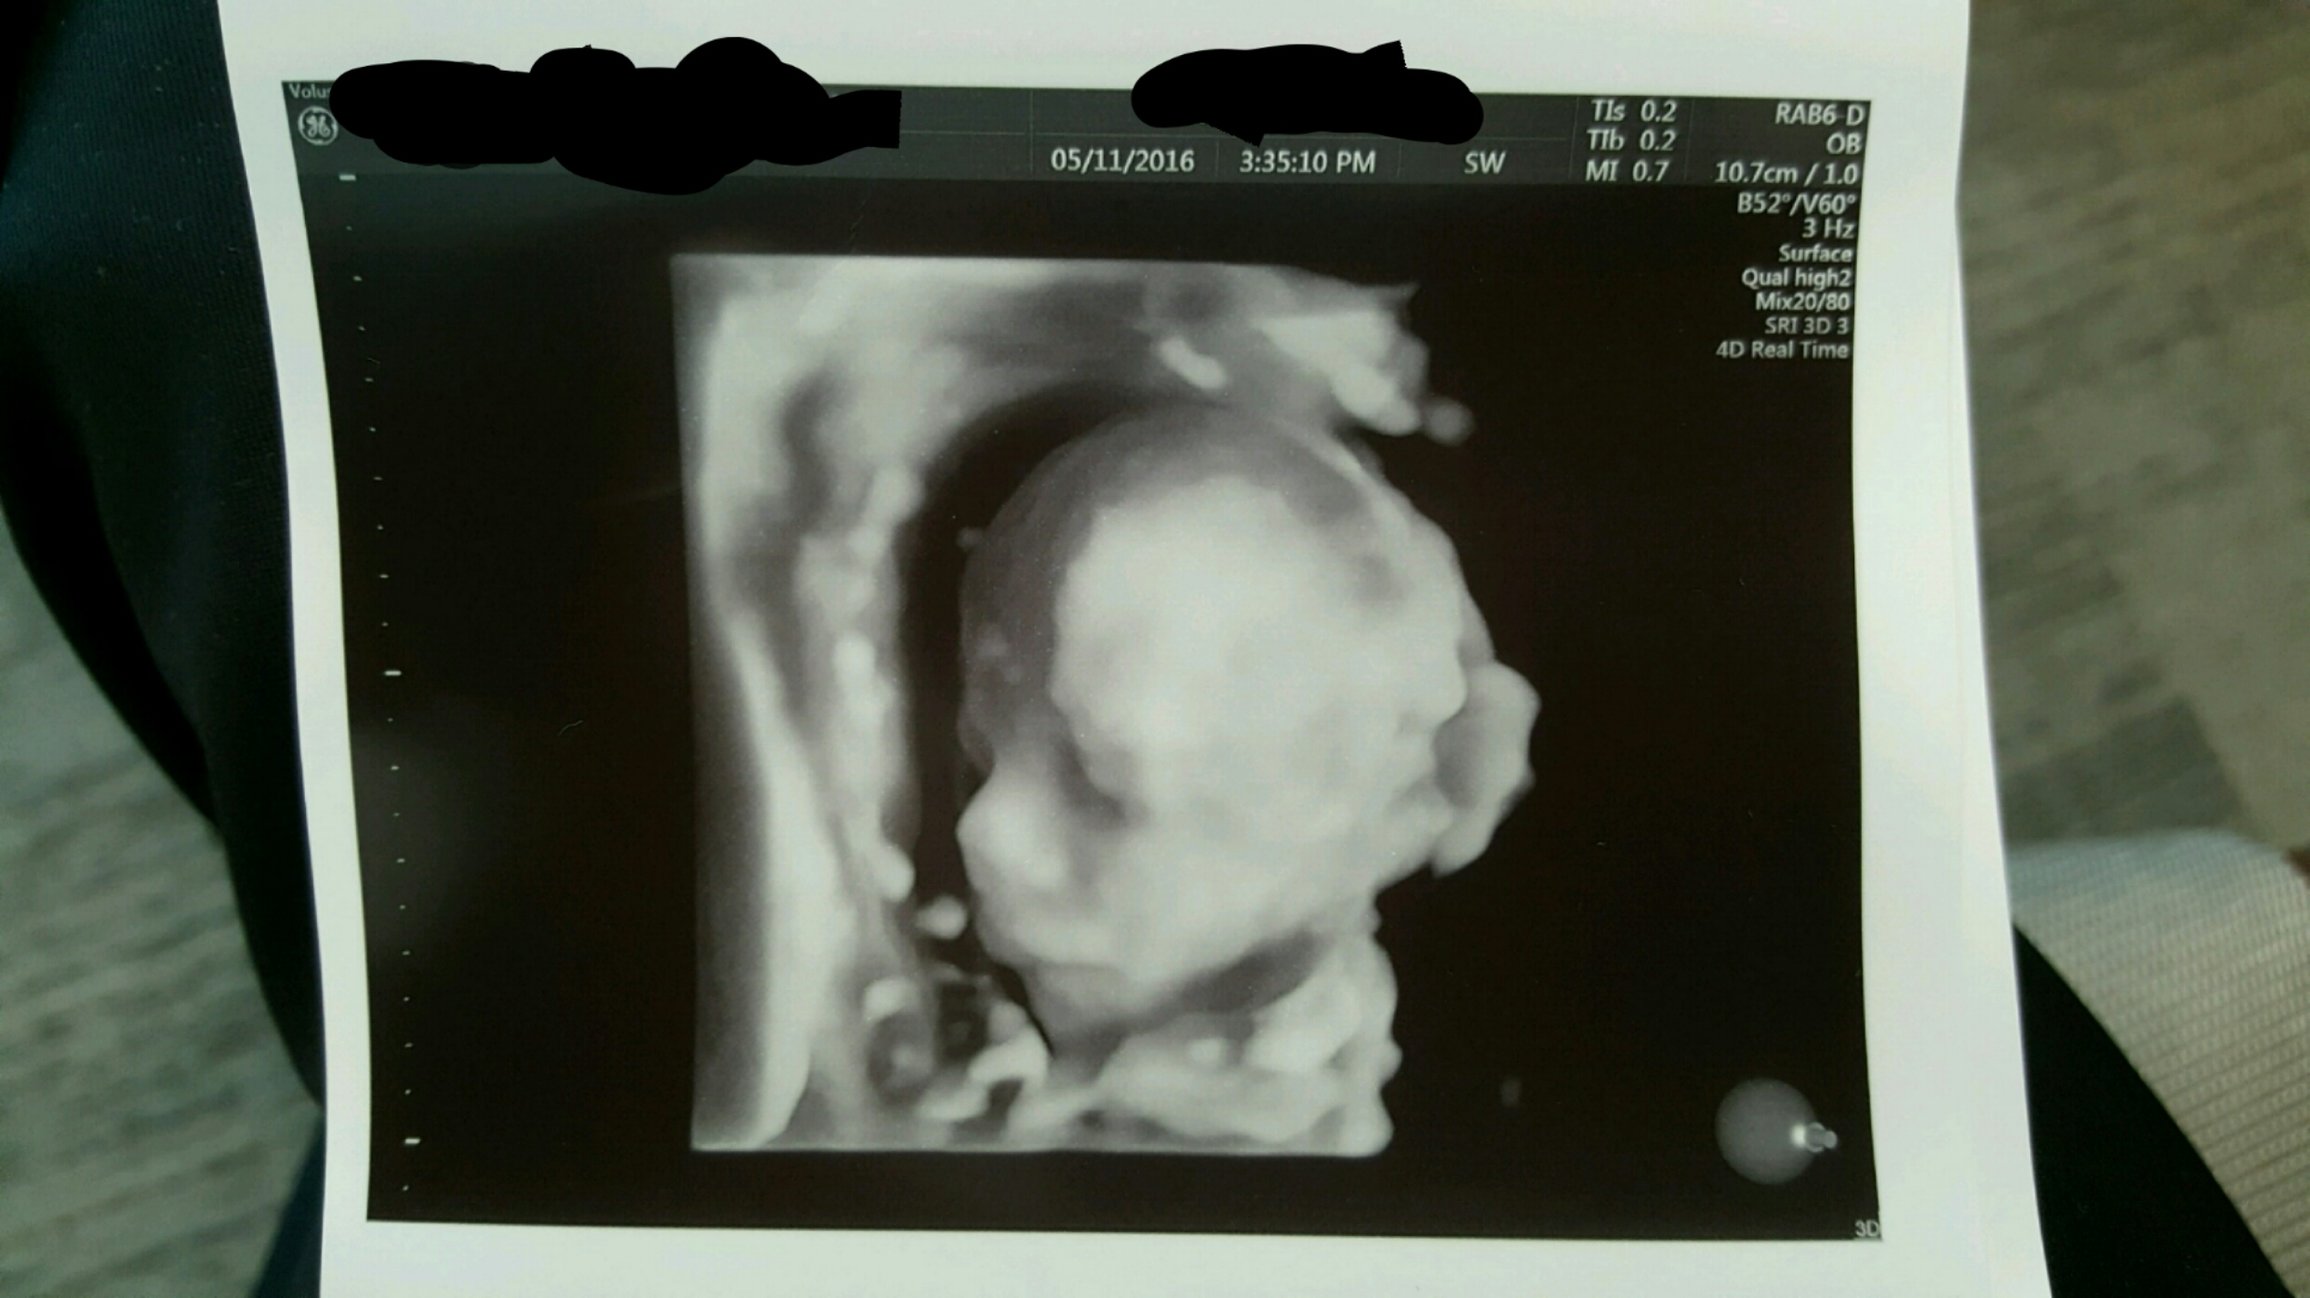

I gave his DH part of his bday present - a trip to the 3D & 4D scan and we were able to see features of our little love. She, so far, is looking more like her momma.

Sorry if giant. 3D ultrasounds are a bit weird but it was so cool to see his face. He has my lips for sure and his daddy's nose. Taken at 25w3d

she looks so content, almost like she's smiling